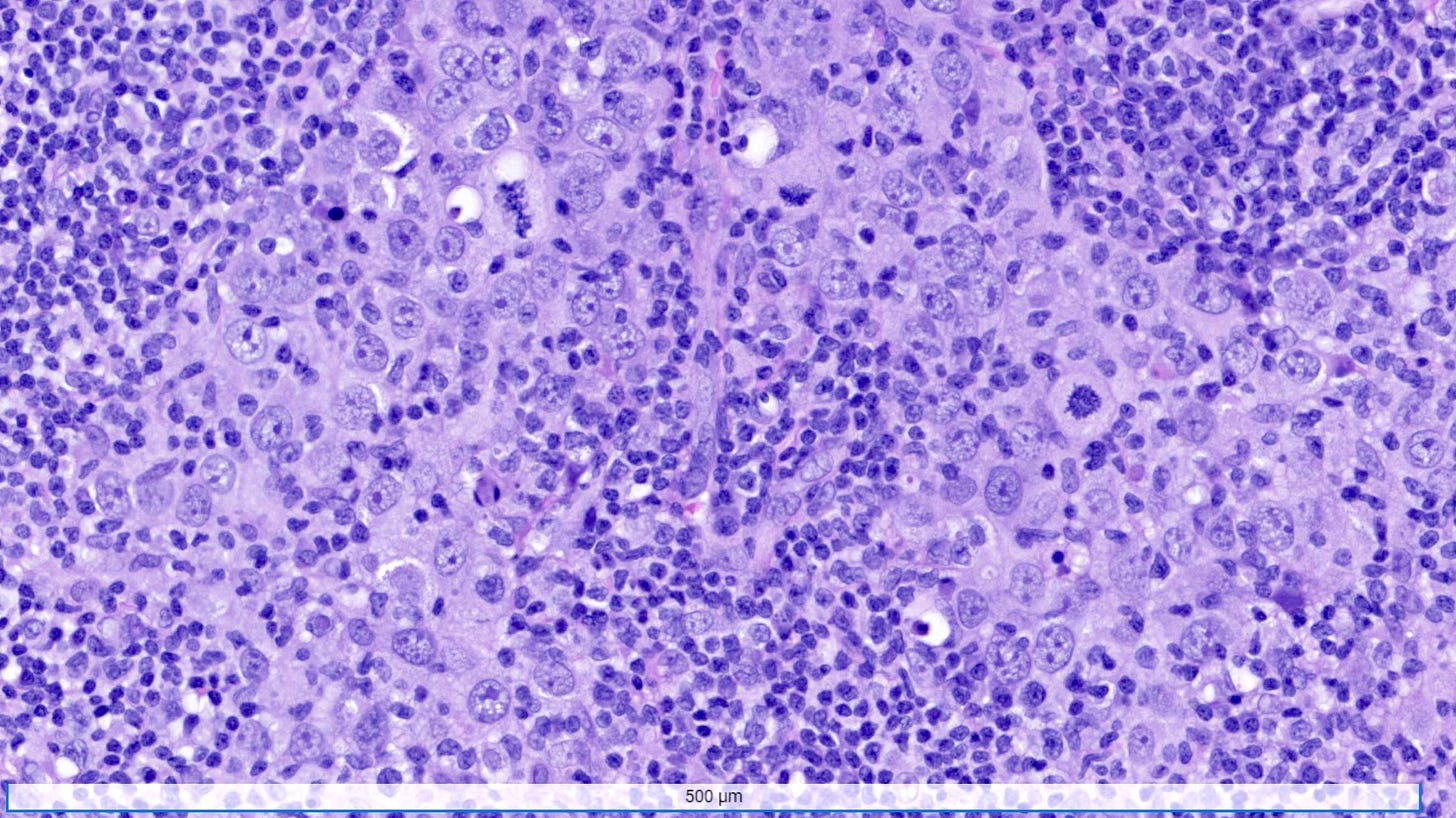

Medullary carcinoma of the breast is a rare subtype (3 - 5%) of invasive breast cancer with pushing borders, syncytial growth, high grade nuclei and a prominent lymphoid infiltrate. According to the World Health Organization, the preferred terminology is invasive breast carcinoma of no special type with medullary pattern.

Microscopically, medullary carcinoma is composed of large, pleomorphic, high grade tumor cells arranged in broad syncytial sheets occupying at least 75% of the tumor area. The tumor cells have vesicular nuclei (i.e., large, pale staining with a central clearing) with prominent nucleoli and abundant eosinophilic cytoplasm. A prominent and dense lymphoplasmacytic infiltrate surrounds and often infiltrates the tumor, suggesting a vigorous host immune response. Mitotic figures are numerous and areas of necrosis may be present.

Medullary carcinoma - radiologic and microscopic images